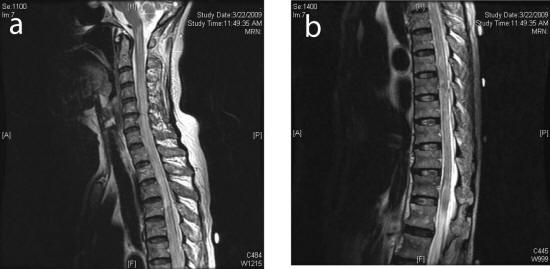

Vascular Myelopathy - Wikipedia, The Free Encyclopedia

Vascular myelopathy (vascular disease of the spinal cord) Spinal cord infarction Edit. Anterior spinal artery syndrome Edit In diagnosis, other causes of abrupt paralysis should be excluded such as cord compression, ... Read Article

Spinal cord infarction - New Zealand Medical Student Journal

Anterior Spinal Cord Infarction. CAUSES OF SCI There are so many reported causes for SCI, and so it is easier to think about most of them according to the pathophysiology of the infarction. When it comes to causes of SCI, it is not much different from stroke in ... Read More

Spinal Cord Infarction And Differential Diagnosis

Still spinal cord infarction (SCI) represents one of the most common causes of acute non-compressive myelopathies [2]. Despite extensive diagnostic efforts, 35–60 % [1, 3] of acute spontaneous spinal cord syndromes remain etiologically ambiguous. ... View Document